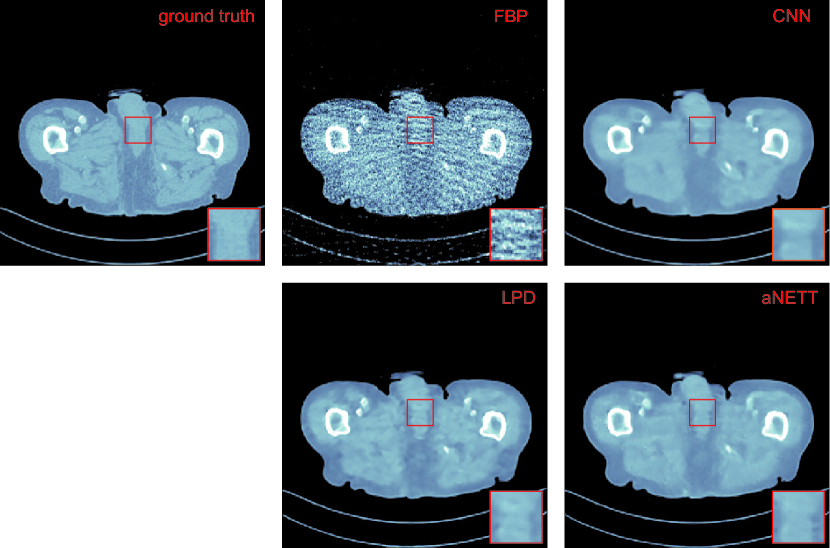

Refer to caption

Figure 4.1: Reconstructions for sparse view CT data from Nφ=40subscript𝑁𝜑40N_{\varphi}=40 angular directions. The intensity range of all images is [500,500]500500[-500,500] HU.

• Sparse View CT: To simulate sparse view data we evaluate the Radon transform for Nφ=40subscript𝑁𝜑40N_{\varphi}=40 directions. We generate noisy data yδ=𝐊x+ηδsuperscript𝑦𝛿𝐊𝑥superscript𝜂𝛿y^{\delta}=\mathbf{K}x+\eta^{\delta} by adding Gaussian white noise with standard deviation taken as 0.020.020.02 times the mean value of 𝐊x𝐊𝑥\mathbf{K}x. We use the 2superscript2\ell^{2}-norm distance as the similarity measure. Quantitative results evaluated on the test set are shown in Table 4.1. All learning-based methods yield comparable performance in terms of PSNR and clearly outperform FBP. The reconstructions shown in Figure 4.1 indicate that aNETT reconstructions are less smooth than CNN reconstructions and less blocky than LPD reconstructions.

The results show that the proposed aNETT regularization is competitive with prominent deep-learning methods such as LPD and post-processing CNNs. We found that the aNETT does not suffer as much from over-smoothing which is often observed in other deep-learning reconstruction methods. This can for example be seen in Figure 4.2 where the CNN yields an over-smoothed reconstruction and the aNETT reconstruction shows more texture. Besides this, aNETT reconstructions are less blocky than LPD reconstructions. Moreover, aNETT is able to leverage higher sampling rates to reconstruct small details while other deep-learning methods fail to do so. We conjecture that this is due the synergistic interplay of the aNETT regularizer with the data-consistency term in (1.3). In some scenarios, it may not be possible to retrain networks. Especially for learned iterative schemes network training is a time-consuming task. Training aNETT on the other hand is straightforward and, as demonstrated, yields a method which is robust to changes of the forward problem during testing time.